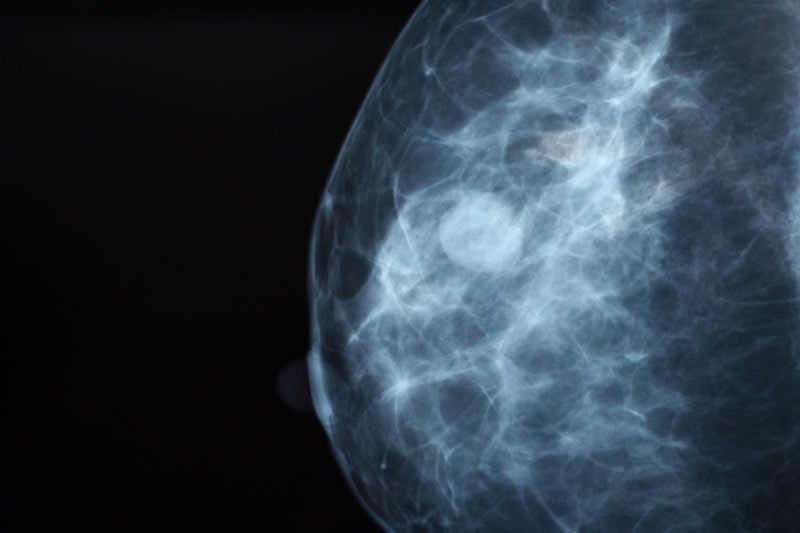

Diagnosis

Early diagnosis through regular screening is key to successful treatment of health conditions related to the breast.

Spotlight on mammograms